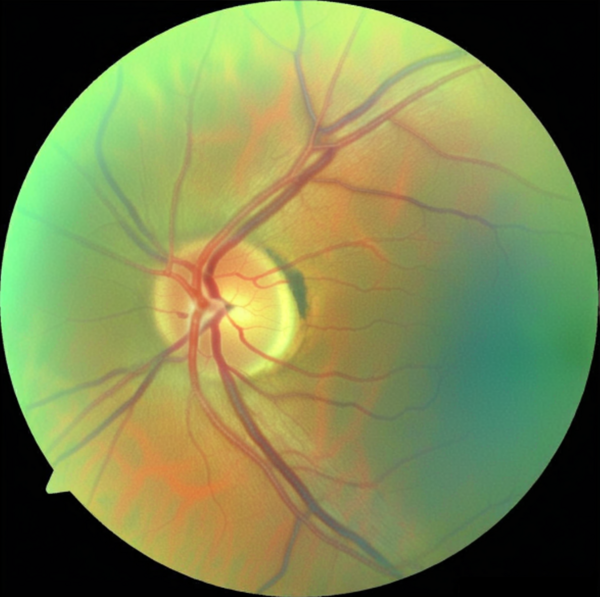

Die führende Klinik für Verletzungen und Erkrankungen der Augen

Von Schielen bis zum Grauen Star – Erkrankungen des Auges sind vielfältig. Viele davon können ambulant behandelt werden, manche erfordern einen stationären Aufenthalt.

In der international anerkannten Klinik für Augenheilkunde Münster behandeln wir Augenverletzungen und -erkrankungen, auch seltener Art, sowohl mit und ohne Operation. Unser Team erfahrener Spezialist*innen in der Augenklinik deckt das komplette Spektrum der Augenheilkunde ab und bietet modernste Untersuchungstechniken und Therapieverfahren.

Unsere Klinik ist als überregionales Laser- und OP-Zentrum führend in der Versorgung von Patient*innen weit über die Grenzen des Münsterlandes hinaus. In drei großen und zwei ambulanten OP-Sälen werden im Jahr rund 7.700 Operationen durchgeführt.

Neben der Versorgung von Notfallpatient*innen bieten wir zahlreiche krankheitsspezifische Sprechstunden wie Netzhaut-, Glaukom- und Hornhautsprechstunde an.